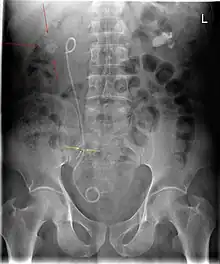

Ureteral pigtail stent  | |

A ureteral stent (pronounced you-REE-ter-ul), or ureteric stent, is a thin tube inserted into the ureter to prevent or treat obstruction of the urine flow from the kidney. The length of the stents used in adult patients varies between 24 and 30 cm. Additionally, stents come in differing diameters or gauges, to fit different size ureters. The stent is usually inserted with the aid of a cystoscope. One or both ends of the stent may be coiled to prevent it from moving out of place; this is called a JJ stent, double J stent or pig-tail stent.